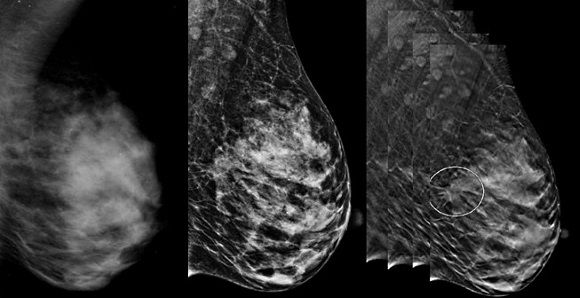

Маммографический томосинтез: Визуальные объяснения